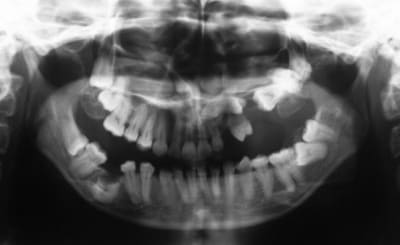

SI joint les photo intra buccal pre traitement et pendant traitement.

Comment expliquer vous le développement ce canting en frontal et de l'open bite en Postérieur ?

Qu'elle est la source du mal ?

Les radio devraient aider un peut mais les photos sont suffisante encore une fois.

La question de base, pourquoi manque-t-il le secteur 2 ? La prémolaire a été extraite comment et pourquoi ? Une pano serait bien quand même....

Photo 1 on met des brackets et fils un ans plus tard Photo 2

Une seul possibilité a ma connaissance qui explique le canting antérieur et l'open bite postérieur.

est ce que ne sont pas des dents ankylosé qui sont la cause de ce resultat a savoir la molaire et la lateral ???

Bingo

Il y avait ankylose de la 22 mais pas des molaires.

Sa se devine ici car le fil est quasiment droit ce qui signifie que sa forme c'est exprimé presque complètement.

Le problème étant que si la forme du fil est correct sa position ne l'est pas.

La 22 étant ankylosé elle a fonctionné comme un point d’appui et a fait bouger tout le reste.

Dans ce cas c'est impressionnant car la dent ankylosé

- était mal positionné en début de traitement

- Qu'il n'y avait aucun dent dans le secteur postérieur pour limiter les effet.

Le fil rond pouvait tourner dans le slot de 22, vue qu'il n'y avait pas de dent en postérieure rien n’empêchait la rotation du fil et donc l’aggravation de la malocclusion.

La 21 qui était proche a était la plus affecté sa se voit bien sur les photo avec bracket, elle a subit une importante rotation dans le sens mesio distal et a était procliner. Son changement de position a eu un impacte sur 21 puis sur 11 ect ect , les effets devenant de plus en plus faible a mesure que l'on s'éloigne.

On a eu une important proclination de l'ensemble des incisive.

Mais encore une fois ce qu'il faut noter c'est le changement important au niveau de 21 avec un FIL PARFAITEMENT DROIT au niveau des incisives

Le dernier cas de ce type que j'ai vue était du a une ankylose de 32 mais vue que les arcades sup et inf était compléte les effet était plus modeste. La 32 était disto versé est avait entrainer une extrusion de 31 et 41 comme d’habitude le schéma était fil quasi droit mais dent qui ne sont pas en bonne position.

Pour savoir ou se situe le problème il y a une règle simple

avec un fil continue vous pouvez facilement réaliser des extrusion mais une intrusion est impossible. Donc pour savoir ou est la dent causal vous chercher la dent qui est en bout de chaîne du groupe de dent ayant subit une extrusion. Le senior qui suivait le cas pensait que la 22 avait subit une intrusion ce qui est une impossibilité biomécanique. La dent qui semble avoir subit une intrusion n'a en fait pas bouger mais a causer l'extrusion de tout le rest, i.e. elle est ankylosée.